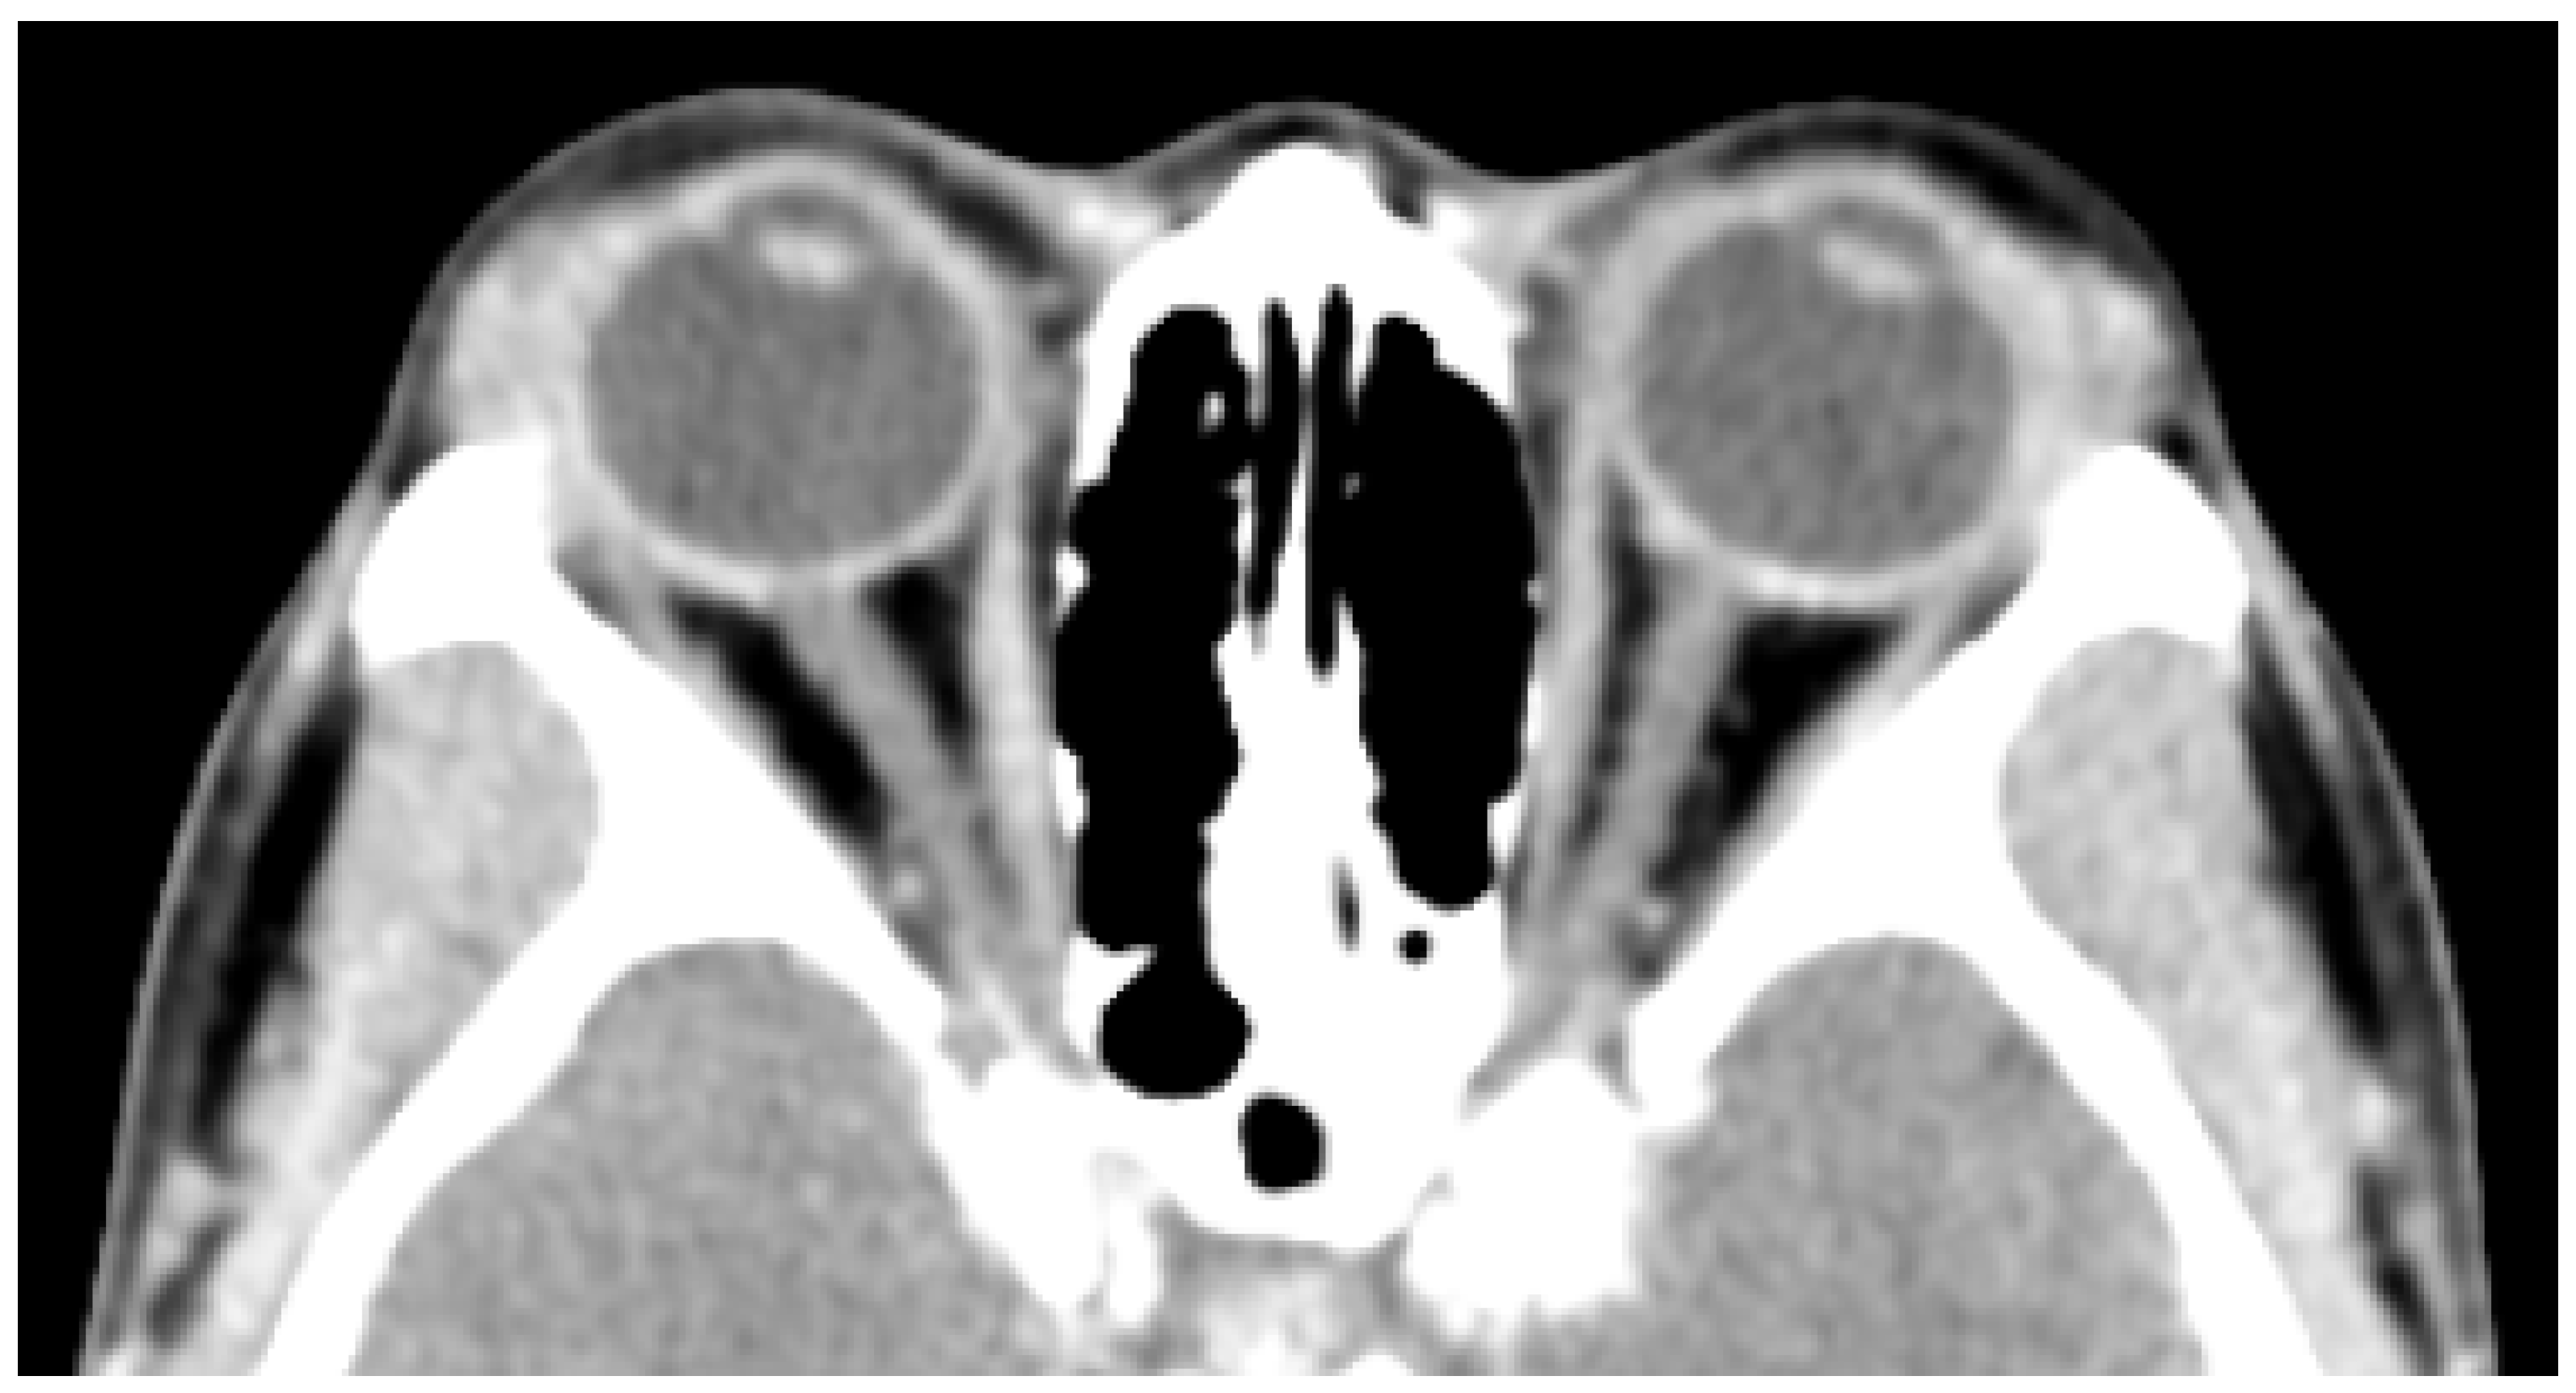

CT scan with contrast of the orbits (Figure 3) shows bilateral symmetrical diffuse hypertrophy of lacrimal glands (arrowheads) measuring at approximately 9mm in thickness.

Figure 3. Axial computed tomography (CT) through the orbits. Arrowheads show lacrimal glands.